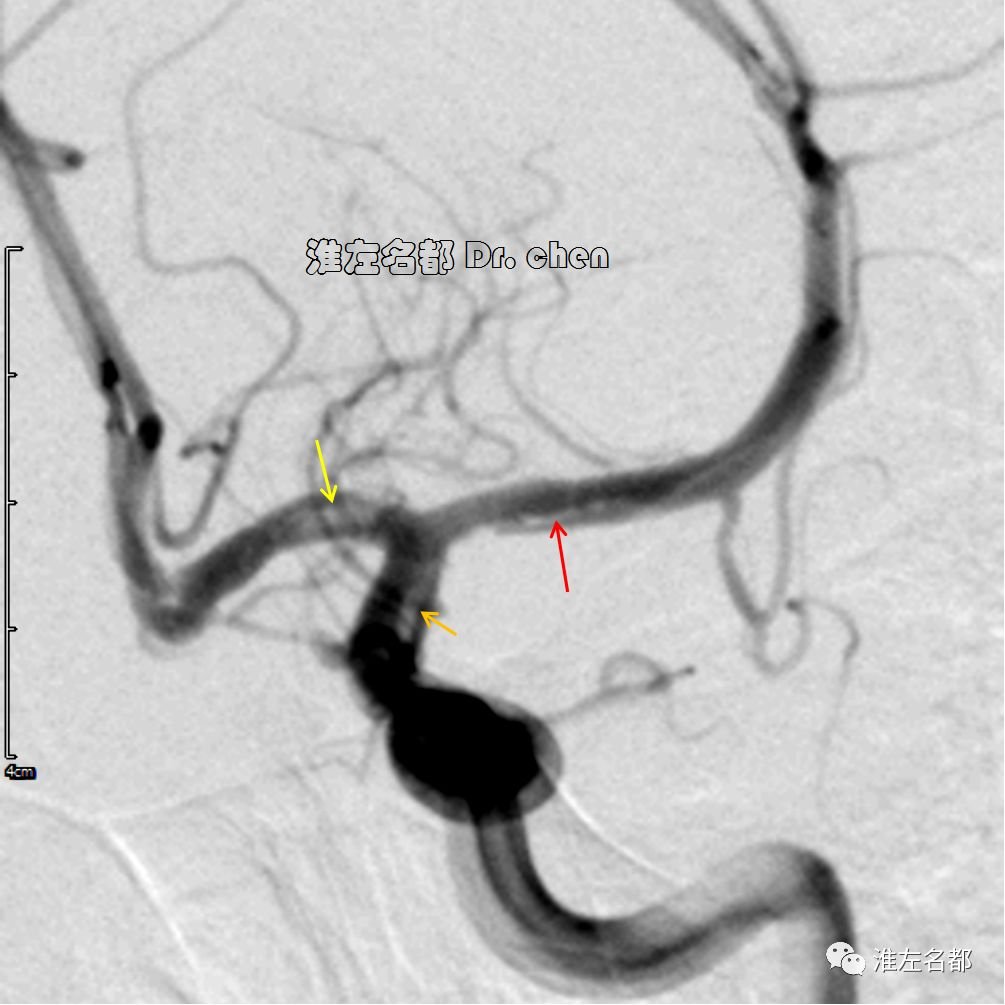

△管壁高分辨MRI(增强T1-SPACE):左侧大脑中动脉主干管壁未见异常(橙箭),左侧颈内动脉远端管壁增厚和强化(红箭)。

△管壁高分辨MRI(增强T1-SPACE):左侧颈内动脉末端检测到夹层“内膜征”(橙箭)。

3.脑动脉夹层临床确诊依赖于影像学检测到典型夹层征象:内膜征/双腔征、长段不规则/丝线样狭窄、壁内血肿、夹层动脉瘤等。本患儿DSA显示左侧颈内动脉末端和大脑中动脉主干长段狭窄,且大脑中动脉主干狭窄呈“丝线样”,符合夹层影像学征象。

6.在夹层真腔得以基本恢复后,DSA于左侧颈内动脉末端、大脑前和中动脉近端均检测到典型“内膜征”,进一步确定了夹层诊断。